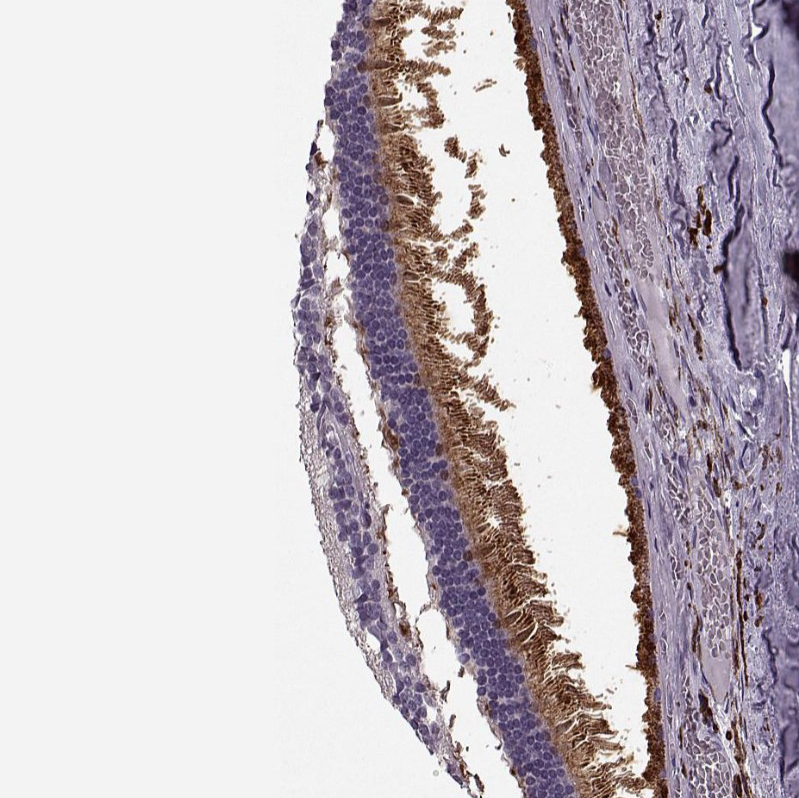

Immunohistochemical staining of human eye,retina shows moderate strong cytoplasmic-membranous positivity.